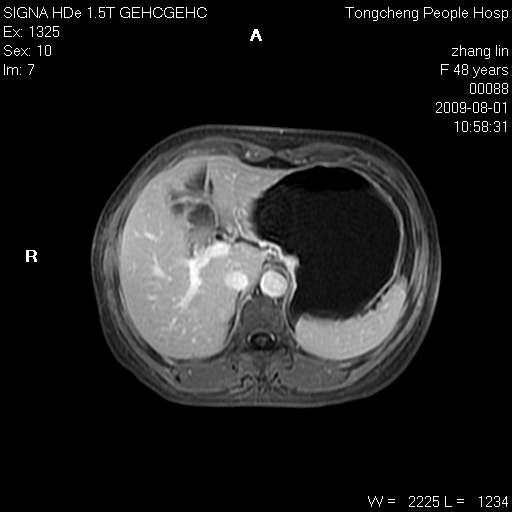

女,48岁。健康体检,彩超发现右肾占位性病变。平素健康。

临床诊断:右肾占位性病变,性质待定(囊肿?肿瘤?)。

上中腹部mr平扫+增强扫描,图像如下:

右肾上极见一类圆形病灶,t1wi呈等信号t2wi呈等高混杂信号,三期增强无强化,边界清---考虑囊肿出血。

同反相位均表现为等信号,病变无强化,考虑含蛋白的囊肿可能,弥散加权相或许有些帮助,

慢性胆囊炎